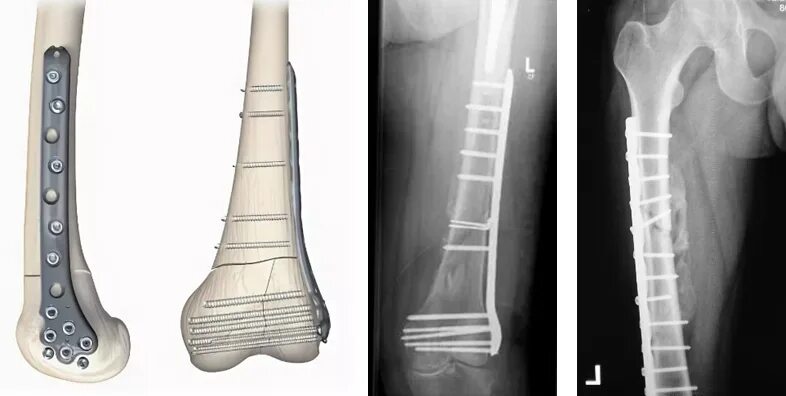

Остеосинтез чрезвертельного перелома